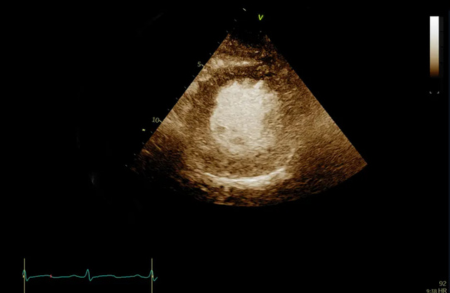

Контрастное исследование левого желудочка